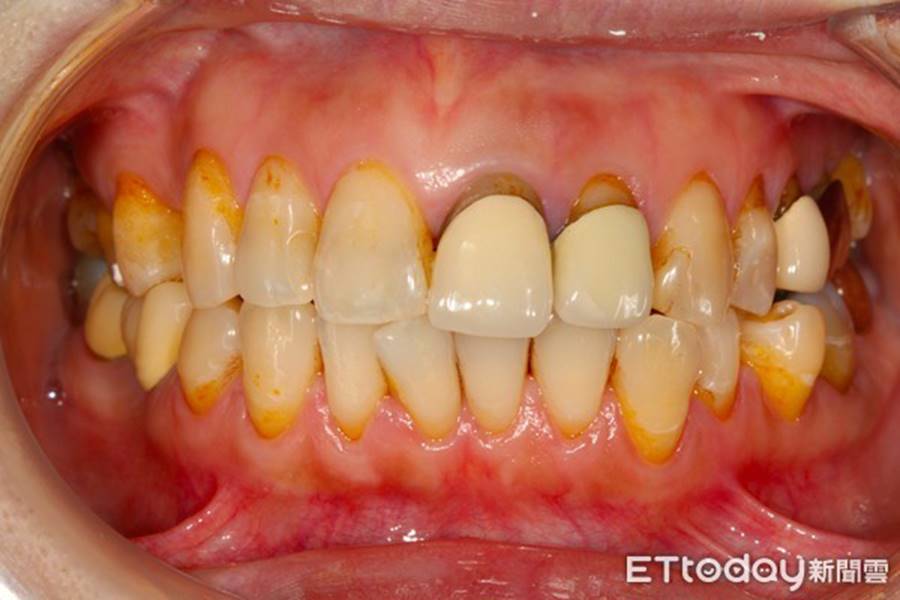

Bác sĩ Hiên nhắc nhở: "Nhiều tiệm trà sữa có thói quen pha thêm chất tạo màu, nếu mỗi ngày bạn đều đặn uống trà sữa hoặc cà phê thì theo thời gian hàm răng của bạn sẽ bị ố vàng, nhìn không đẹp".